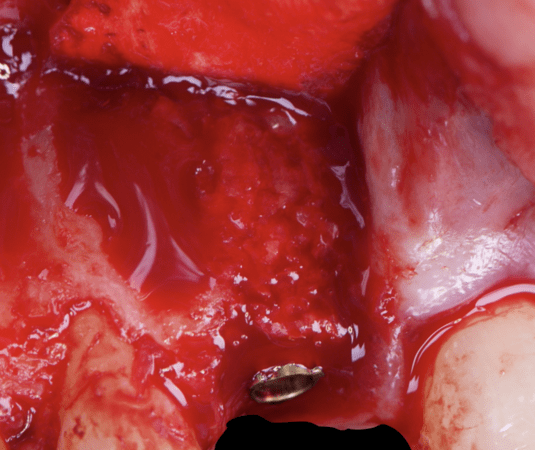

Given the significant buccal defect, guided bone regeneration (GBR) was performed simultaneously. A mixture of autologous bone and creos™ xenogain™ was applied to the defect and covered with a resorbable creos™ membrane to restore ridge width and support the buccal contour. In addition, a connective tissue graft was harvested and placed in the vestibular region to increase the thickness of keratinized mucosa. This combined approach addressed both hard and soft tissue deficiencies, providing the biological foundation for a stable and esthetic outcome.